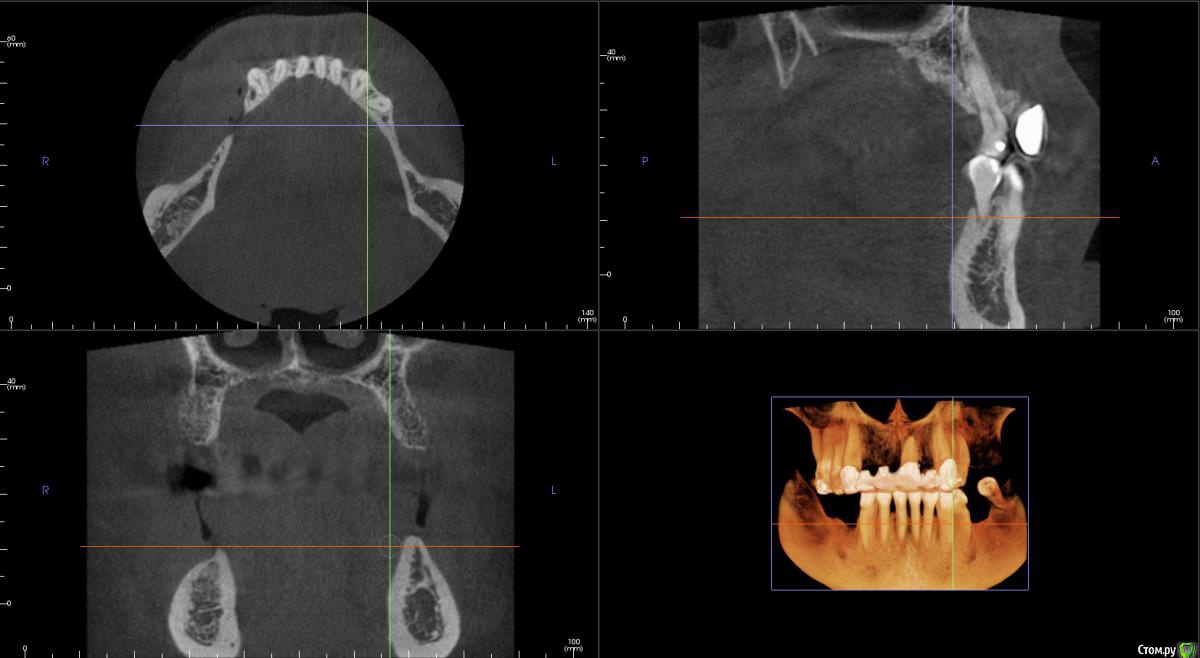

kamranchick Опубликовано 17 февраля, 2015 Поделиться Опубликовано 17 февраля, 2015 Добрый вечер.Имеется следующая проблемаПациент обратлся с жалобами в области отсутствия жевательных зубов, планируется имплантация.Вопросы такого плана, в области 3 сегмента думаю сделать расщепление гребня, установка имплантов 3,75/8 и аугментация костью Ostebiol Gen-Os, мембрана.В области 4 сегмента больше сомнения, планируется титановая сетка +аугментация, либо расщепление опять же, планирую разделить восстановление и имплантауию на 2 этапа в 4 сегментеКакие будут комментарии? Ссылка на комментарий

Shuvalov Опубликовано 17 марта, 2015 Поделиться Опубликовано 17 марта, 2015 Добрый вечер.Имеется следующая проблемаПациент обратлся с жалобами в области отсутствия жевательных зубов, планируется имплантация.Вопросы такого плана, в области 3 сегмента думаю сделать расщепление гребня, установка имплантов 3,75/8 и аугментация костью Ostebiol Gen-Os, мембрана.В области 4 сегмента больше сомнения, планируется титановая сетка +аугментация, либо расщепление опять же, планирую разделить восстановление и имплантауию на 2 этапа в 4 сегментеКакие будут комментарии?Думаю Mane прав И получите прогнозируемый результат! Без сетки! Сосиска рулит Ссылка на комментарий